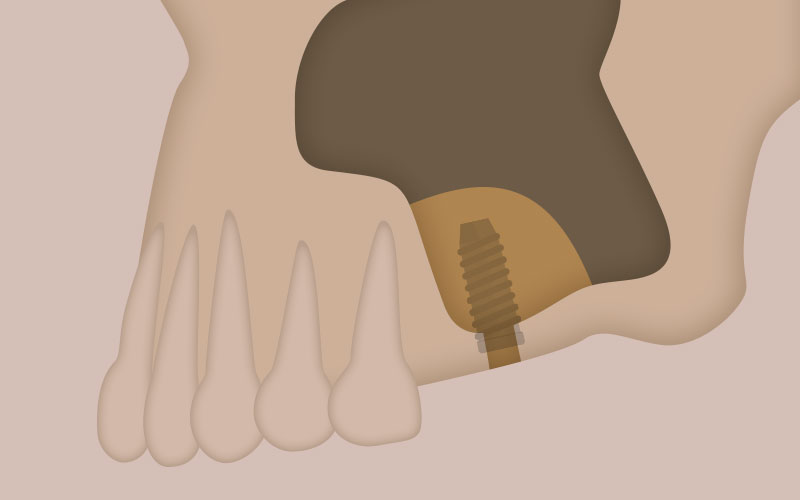

CASE.03

GBR(骨再生誘導)

歯を失って、時間が経つと、しだいに周りの歯槽骨が吸収されていきます。歯槽骨が足りない部分に、粉砕した自家骨あるいは骨補填材をおき、その上に人工膜をおきます。歯肉などの柔らかい組織が入ってこなくなるので、骨の再生が促されます。